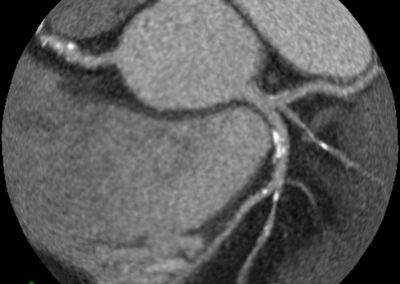

στεφανιογραφία στον αξονικό τομογράφο.

Τρισδιάστατη και δισδιάστατη απεικόνιση των στεφανιαίων αγγείων όπου διακρίνεται σημαντικότατη στένωση της δεξιάς στεφανιαίας αρτηρίας λίγο πριν το προϋπάρχον stent, το οποίο απεικονίζεται φυσιολογικά βατό